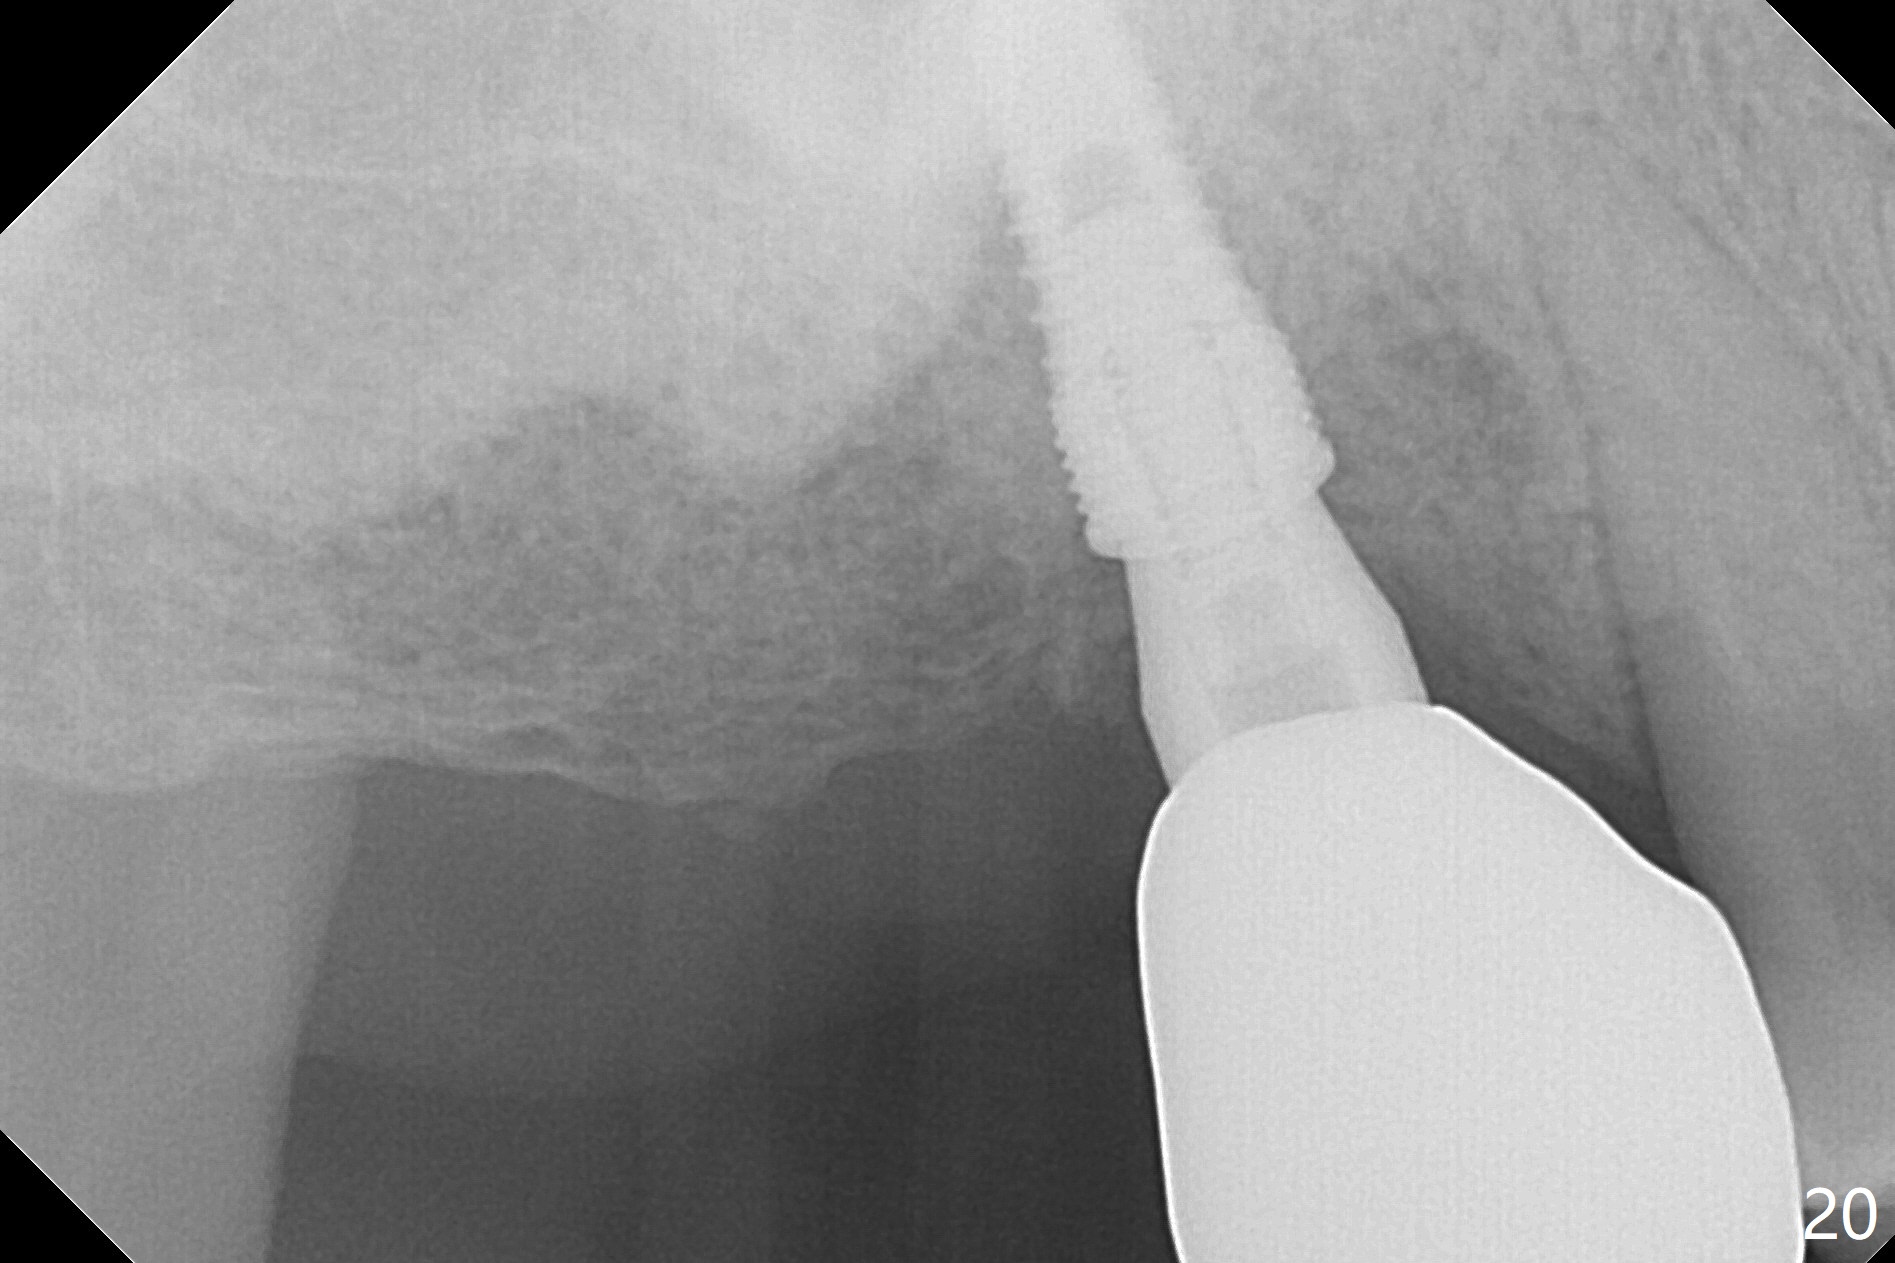

Two weeks later, the buccal gingiva appears to have grown downward (Fig.13). Fig.14 is taken when the provisional is removed. To facilitate this process, change abutment from 4.8x7(3) to (4.5) mm and a new provisional is fabricated (Fig.15): note the metal exposure distobuccally. When the patient returns in another two week, the gap should be able to disappear. There is no loss of bone graft 3 months postop (Fig.16). Two weeks later (3.5 months postop), the margin of the abutment is supragingival buccally and subgingival palatally (Fig.17,18). The gingiva seems to have migrated downward (Fig.19 arrow), while the bone density around the coronal implant appears to increase 5.5 months post cementation (Fig.20). There is buccal swelling with purulent discharge 1.5 years post cementation (Fig.21). Perimplantitis develops. Tuberosis bone graft will be performed when the limited ortho is finished.